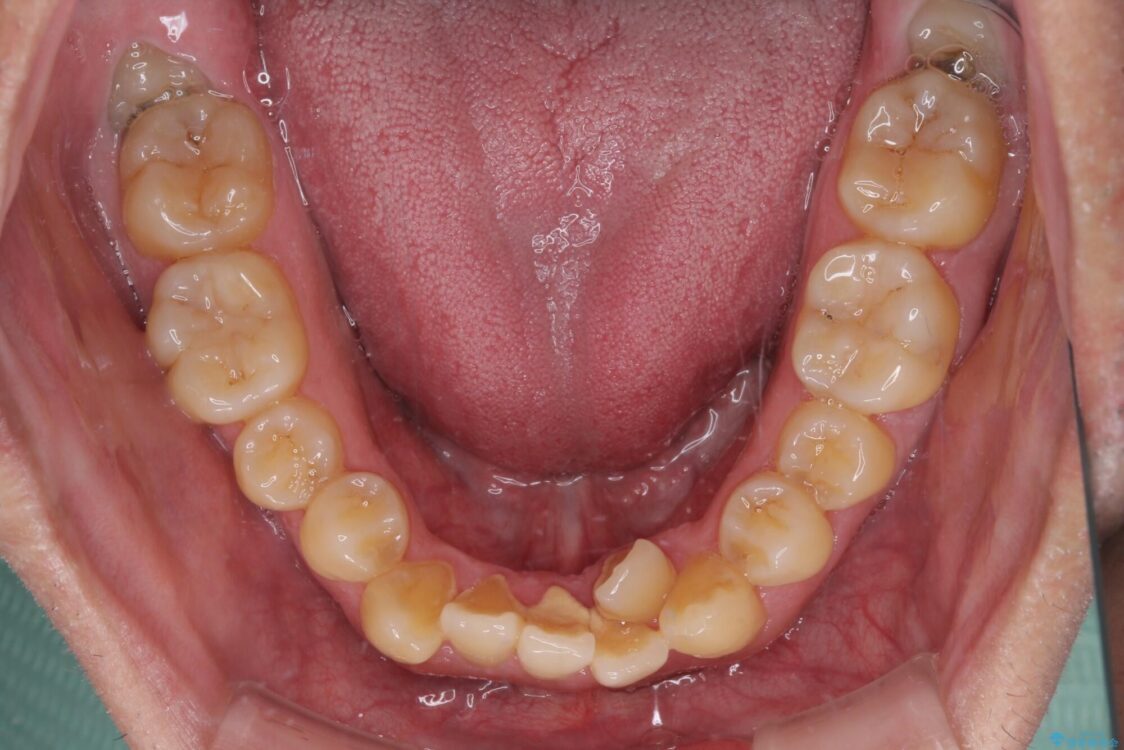

治療途中

• 八重歯とクロスバイト 目立たないワイヤー装置で矯正治療 治療途中画像

クロスバイトは、治療の過程で咬み合わせが大きく変化する期間があり、食事が取りにくくなってしまいます。

また、装置が対合歯と咬み合ってしまい、頻繁に脱落するなど、色々と面倒なことがあり、治療がスムーズに進まないことがあります。

デコボコが解消されると歯列が拡大される方向に動くため、出っ歯のような仕上がりとなることがあります。舌の突出癖を改善するトレーニングをしっかりと行っていただくことで、突出を抑制することができます。